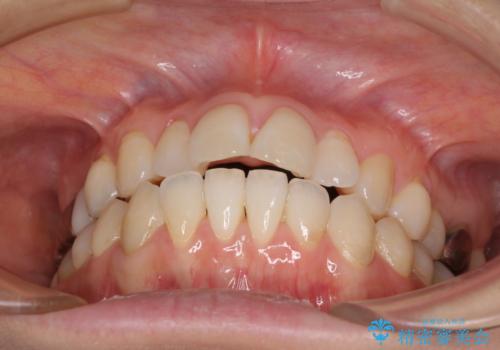

- 捻れた前歯と目立つ銀歯を気にして来院された患者様です。

歯列不正は軽微であったため、インビザライン・ライトにて改善することとしました。

左下大臼歯は根管治療が必要であったため、矯正治療前に根管治療を行い、その後矯正治療を行うこととしました。

矯正治療後には期にある銀歯を全てセラミッククラウンなどで補綴治療することとしました。

インビザライン・ライトによる矯正治療であったので、時間をかけずに治療を終えることができました。

口を開ける度に目立っていた銀歯もセラミックで自然な口元の印象となりました。